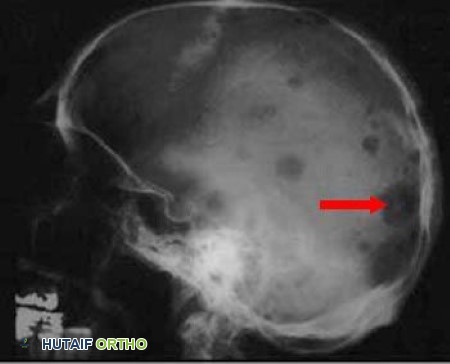

يُطلق اسم "الورم النقوي المتعدد" على هذا السرطان بناءً على المظهر المميز لخلاياه السرطانية تحت المجهر، والذي يشبه "وجه الساعة". تتسلل هذه الخلايا السرطانية إلى نخاع العظم، وهو المركز الإسفنجي للعظام حيث يتم إنتاج خلايا الدم الحمراء والبيضاء، وتنتشر فيه بشكل واسع. في صور الأشعة السينية، يظهر الورم النقوي المتعدد على شكل "ثقوب مثقوبة" في العظم، مما يدل على تآكل العظم وتلفه.

تُظهر صورة الأشعة السينية للجمجمة المأخوذة من الجانب النتائج النموذجية للورم النقوي المتعدد والعديد من "الثقوب المثقوبة". يشير السهم إلى أحد الثقوب الأكبر.